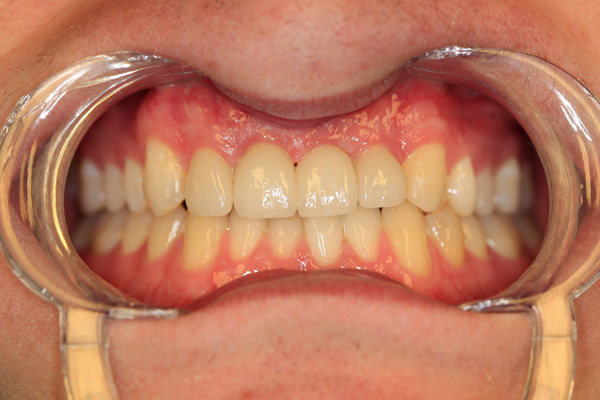

Problem: This young man was hit by a car while riding his bike. He had multiple fractures in his jaw and three front teeth were fractured.

Plan: Our plan… his fractures were fixed. The trauma left a bony defect which was grafted as well as soft tissue VIP grafts. Placed three separate implants with guided surgery. Molded the tissue and placed Zirconium abutments with porcelain crowns.

A great young man with a confident smile.